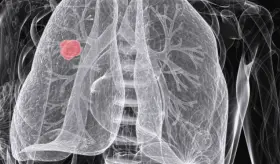

El cáncer de pulmón debe enfrentarse con dos pilares: la prevención, que incluye reducir la exposición al tabaco, contaminantes ambientales y riesgos laborales y la detección temprana, porque es este diagnóstico precoz el que realmente salva vidas.

En la isla, más de ochocientos nuevos casos son diagnosticados anualmente, siendo el tercer cáncer más común en hombres y el quinto en mujeres, lo que subraya la urgencia de esta iniciativa.